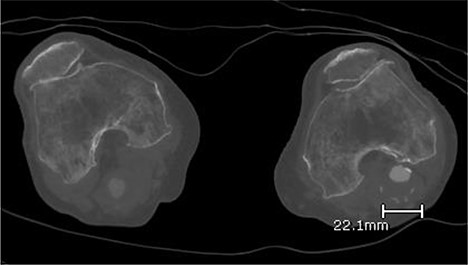

A 92-year-old female, independent from home, presented after multiple falls due to a four-month history of left foot drop. The foot drop had gradually worsened to the point that there was complete paralysis of ankle dorsiflexion and was associated with significant oedema of the foot. On examination, there was a large pulsatile mass in the popliteal fossa bilaterally. All peripheral pulses were palpable without any signs of ischemia. The most striking examination finding was complete paralysis of left ankle dorsiflexion with 0 out of 5 power. Ultrasound revealed that there were (Fig 1) bilateral popliteal artery aneurysms, which was larger on the left, causing displacement and impingement of the common peroneal nerve at the knee crease (Fig 2). Further computed tomography angiogram demonstrated an unruptured left PAA measuring 22 × 21 mm in maximal dimension over a distance of 24 mm (Fig 3). Intraluminal thrombus was also noted with 60% luminal stenosis. Distally, the arteries were heavily calcified with two-vessel runoff at the ankle. An emergency endovascular repair of the left PAA was performed by using 8 mm × 15 cm and 7 mm × 10 cm Gore Viabahn stents (Fig 4). The stents were deployed after a balloon-angioplasty and adequate decompression of the aneurysm was achieved. The postoperative period was uneventful, and patient’s pre-existing aspirin was continued. The leg and foot oedema improved rapidly over the subsequent few days. At follow-up in 12 weeks, the patient showed some return of motor function of the ankle and was walking with ankle splint. Her left leg remained well perfused with palpable pulses.

Digital subtraction angiogram image of the endovascular repair of left popliteal artery aneurysm with 8 mm × 15 cm and 7 mm × 10 cm Gore Viabahn stents.